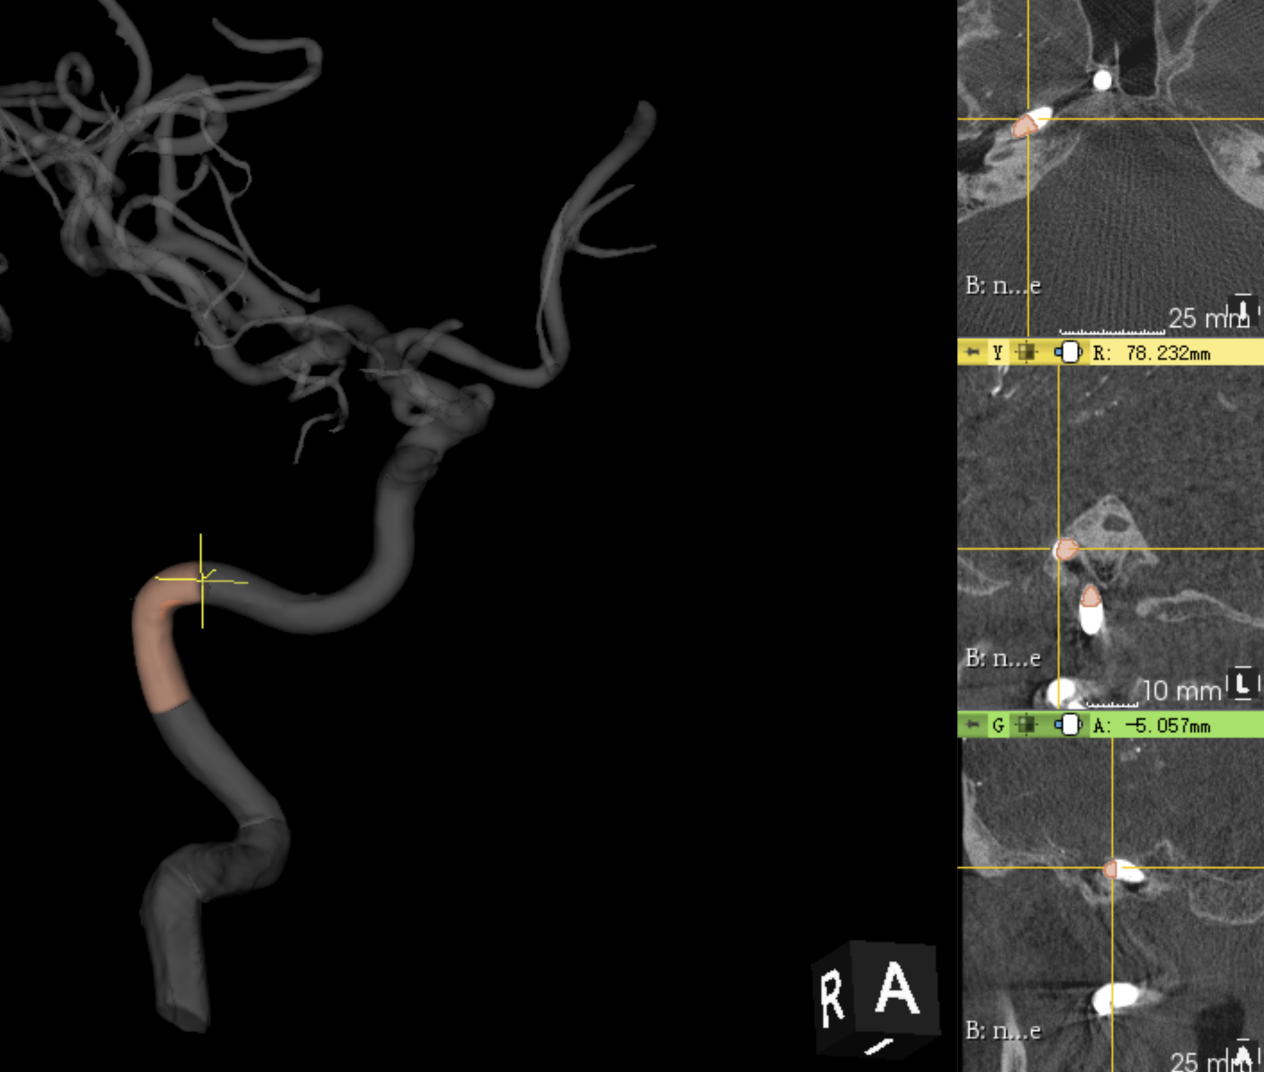

颈内动脉ICA分段(七分法)颈内动脉分段有两种分法,一种是“逆血流法”,由Fisher在1938年提出的5段分法另一种是“顺血流法”,由Bouthillier等在1996年提出的7段分法,以数字(C1-C7)顺着血流方向标记颈内动脉全程,该分法对神经外科具有重要的解剖意义

48440f0d9fe46d1700062caf71257c63.png

C1颈段起于颈总动脉分叉水平,终止于颈动脉管颅外口(如下图中黄十字架)

6c67159efa93b88fd0fc5de16d655c69.png

C2岩骨段这段颈内动脉位于颈动脉管内,起于颈动脉管颅外口,终止于破裂孔后缘(黄色十字架)

b543e955e7c225920ec64e3d3243e84e.png

C3破裂孔段起于颈动脉管末端,在破裂孔的垂直管内上升,向着海绵后窦,止于岩舌韧带上缘

e68ffafee2d0dd90f19ebd850341e0dc.png

C4海绵窦段此段始于岩舌韧带上缘,止于近侧硬膜环

1f23a1229919ee643696f3387d1442c4.png

床段(C5)此段起于近侧硬膜环,止于远侧硬膜环。床段短,长约4~6mm,斜行于外侧前床突和内侧颈动脉沟之间。床段C5属于硬膜外结构

85753a0b1998e549135a8c33da88d1b1.png

C6眼段该段起于远侧硬膜环,止于后交通动脉起点的近侧

964338a8b3a004dc5e060cc0a35e67cf.png

C7交通段交通段起于紧靠后交通动脉起点的近侧,止于颈内动脉分叉处